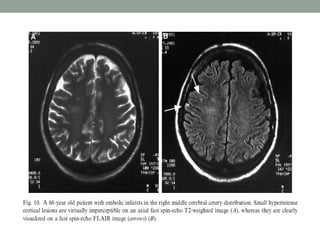

• T2-weighted imaging is well suited for lesion detection in

the brain because most lesions appear hyperintense with

this sequence.

• However CSF also appears hyperintense on T2-weighted

spin-echo (SE) images.

• Therefore, lesions at CSF interfaces, such as cortical sulci

and ventricles, may be mistaken for extensions of CSF or

partial volume effects.

• FLAIR imaging suppresses signal from free water in CSF

and maintains hyperintense lesion contrast.

• FLAIR image have a long TR and TE and an inversion

time (TI) that is tailored to null the signal from CSF.

• FLAIR sequences are particularly useful in evaluation of

MS, infarcts, SAH